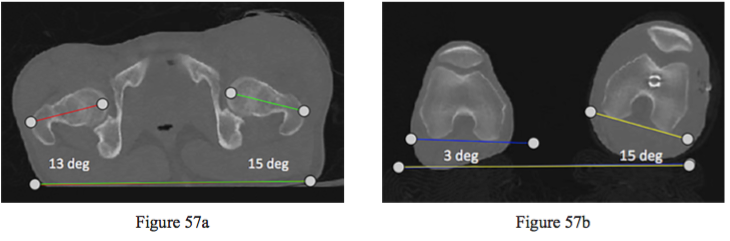

Figures 57a and 57b are the CT scanograms of a 24-year-old man who was shot in the left thigh. He sustained an isolated comminuted femoral shaft fracture. After performing a locked intramedullary nail procedure, the scanogram was taken to check rotational alignment. After reading the scanogram, what is the best next step?

PREFERRED RESPONSE: 3